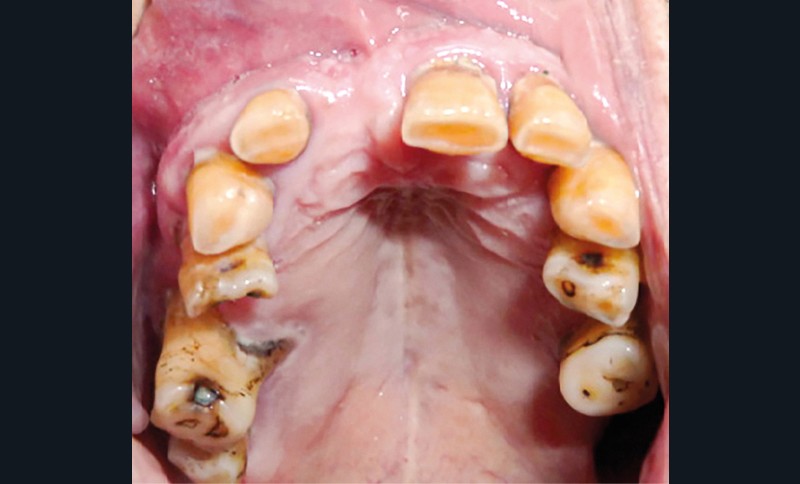

L’examen intra-oral montre un comblement au fond du vestibule au niveau de tout le secteur antérieur depuis l’incisive centrale gauche (21) jusqu’à la première prémolaire droite (14), la muqueuse est d’aspect sain (fig. 4). La palpation vestibulaire haute révèle une masse élastique sous-muqueuse située au niveau du plancher nasal antérieur, dépressible et légèrement douloureuse.

L’origine dentaire a été écartée par la clinique (aucun antécédent de douleurs dentaires et le test de vitalité pulpaire est positif sur les dents antérieures) et par l’orthopantomogramme, qui n’a révélé aucune modification des structures osseuses.